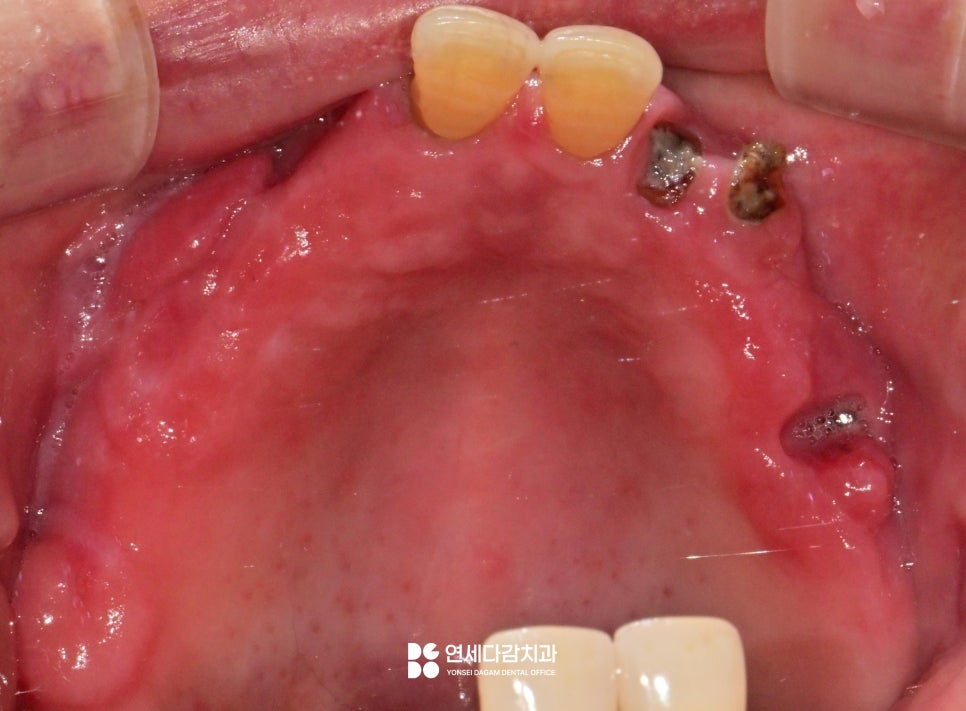

다만, 지금처럼 치아 자체의 손상이 크거나

골 손실량이 너무 많은 경우에는

예후가 좋지 않아 발치를 고려해야 됩니다.

2026.01.19

해당 구강의 저작, 심미성을 회복하기 위해

임플란트를 계획해 볼 수 있습니다.